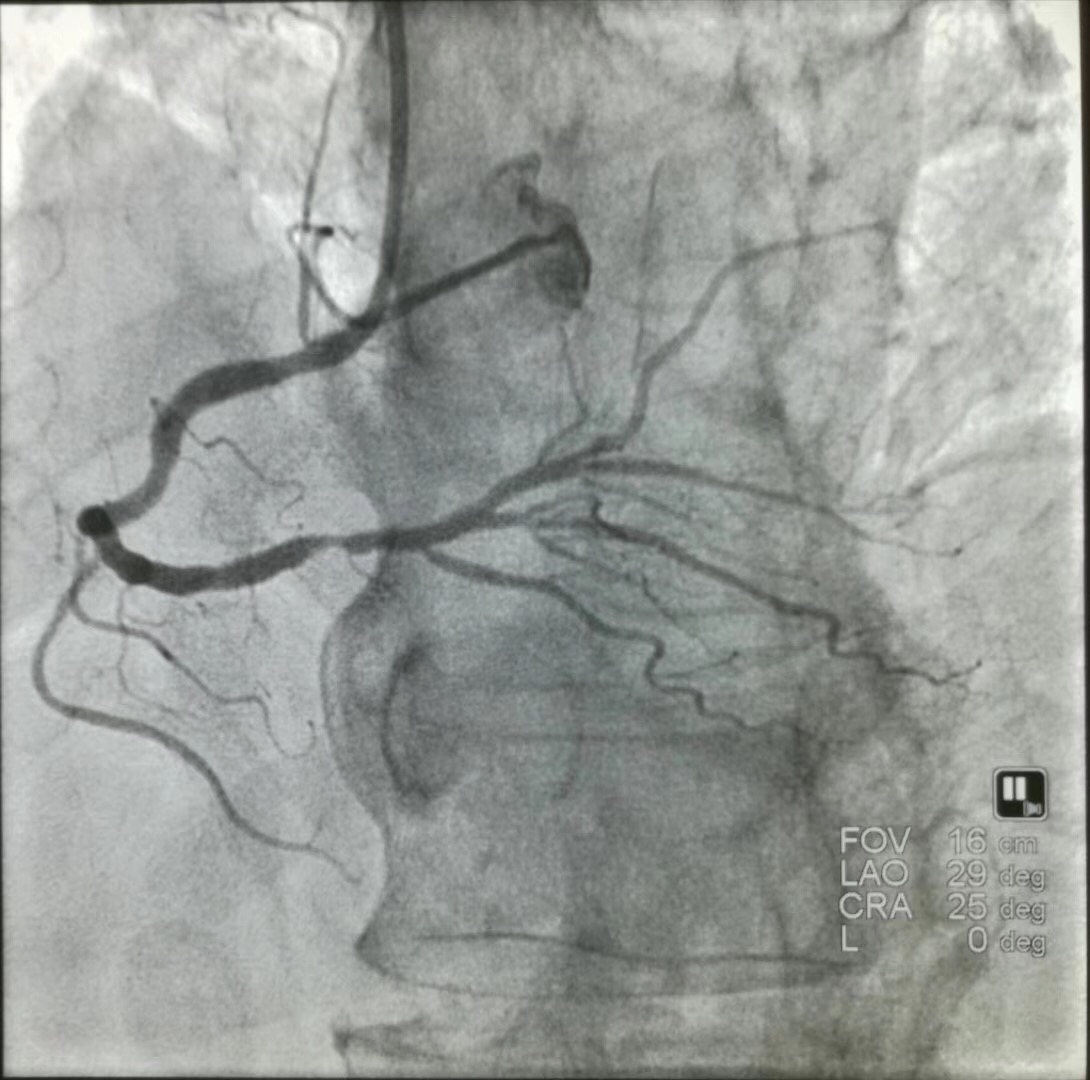

冠脉造影

如果是血管内超声,是可以诊断冠心病的,还可以直接观察斑块的性质、形态等,更直观,但缺点是属于有创检查,价格昂贵且技术要求条件高只能在部分三甲医院做。如果是普通的心超,如果发现有心肌的阶段性活动异常、反向运动(室壁瘤)等的影像,均提示可能有冠心病,但仍需冠脉CTA或冠脉造影进一步明确。